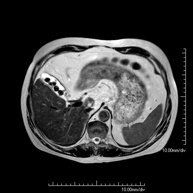

Prova diagnòstica no invasiva que consisteix en l'obtenció d'imatges d'alta definició anatòmica de l'abdomen mitjançant l'ús d'un camp electromagnètic i ones de ràdio (amb un emissor i un receptor). No utilitza radiació ionitzant. En aquesta exploració s'inclouen el fetge, el pàncrees, la melsa, la via biliar, la vesícula biliar, les glàndules suprarenals, els ronyons, l'aorta abdominal, la vena cava inferior, l'estómac, el duodè, etc. En alguns casos caldrà emprar contrast paramagnètic (Gadolini) per caracteritzar les lesions. - RM Pelvis femenina

Prova diagnòstica no invasiva que consisteix en l'obtenció d'imatges d'alta definició anatòmica del fetge mitjançant l'ús d'un camp electromagnètic i ones de ràdio (amb un emissor i un receptor). No utilitza radiació ionitzant. Es realitza per estudiar qualsevol lesió localitzada en el fetge. Normalment es requereix l'ús de contrast paramagnètic (Gadolini) per caracteritzar les lesions. És necessari realitzat la prova en dejú (6 hores). - RM de Ronyons

Prueba diagnóstica no invasiva que consiste en la obtención de imágenes de alta definición anatómica del abdomen mediante el empleo de un campo electromagnético y ondas de radio (con un emisor y un receptor). No utiliza radiación ionizante. En esta exploración se incluyen el hígado, páncreas, bazo, vía biliar, vesícula biliar, glándulas suprarrenales, riñones, aorta abdominal, vena cava inferior, estómago, duodeno, etc. En ocasiones se deberá emplear contraste paramagnético (Gadolinio) para caracterizar las lesiones. - URO-RM